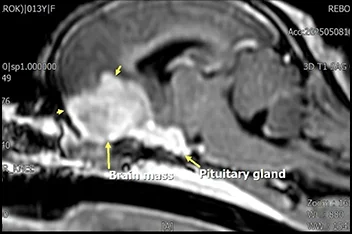

신경계종양(뇌&척수종양)

종양절제술

• 뇌종양